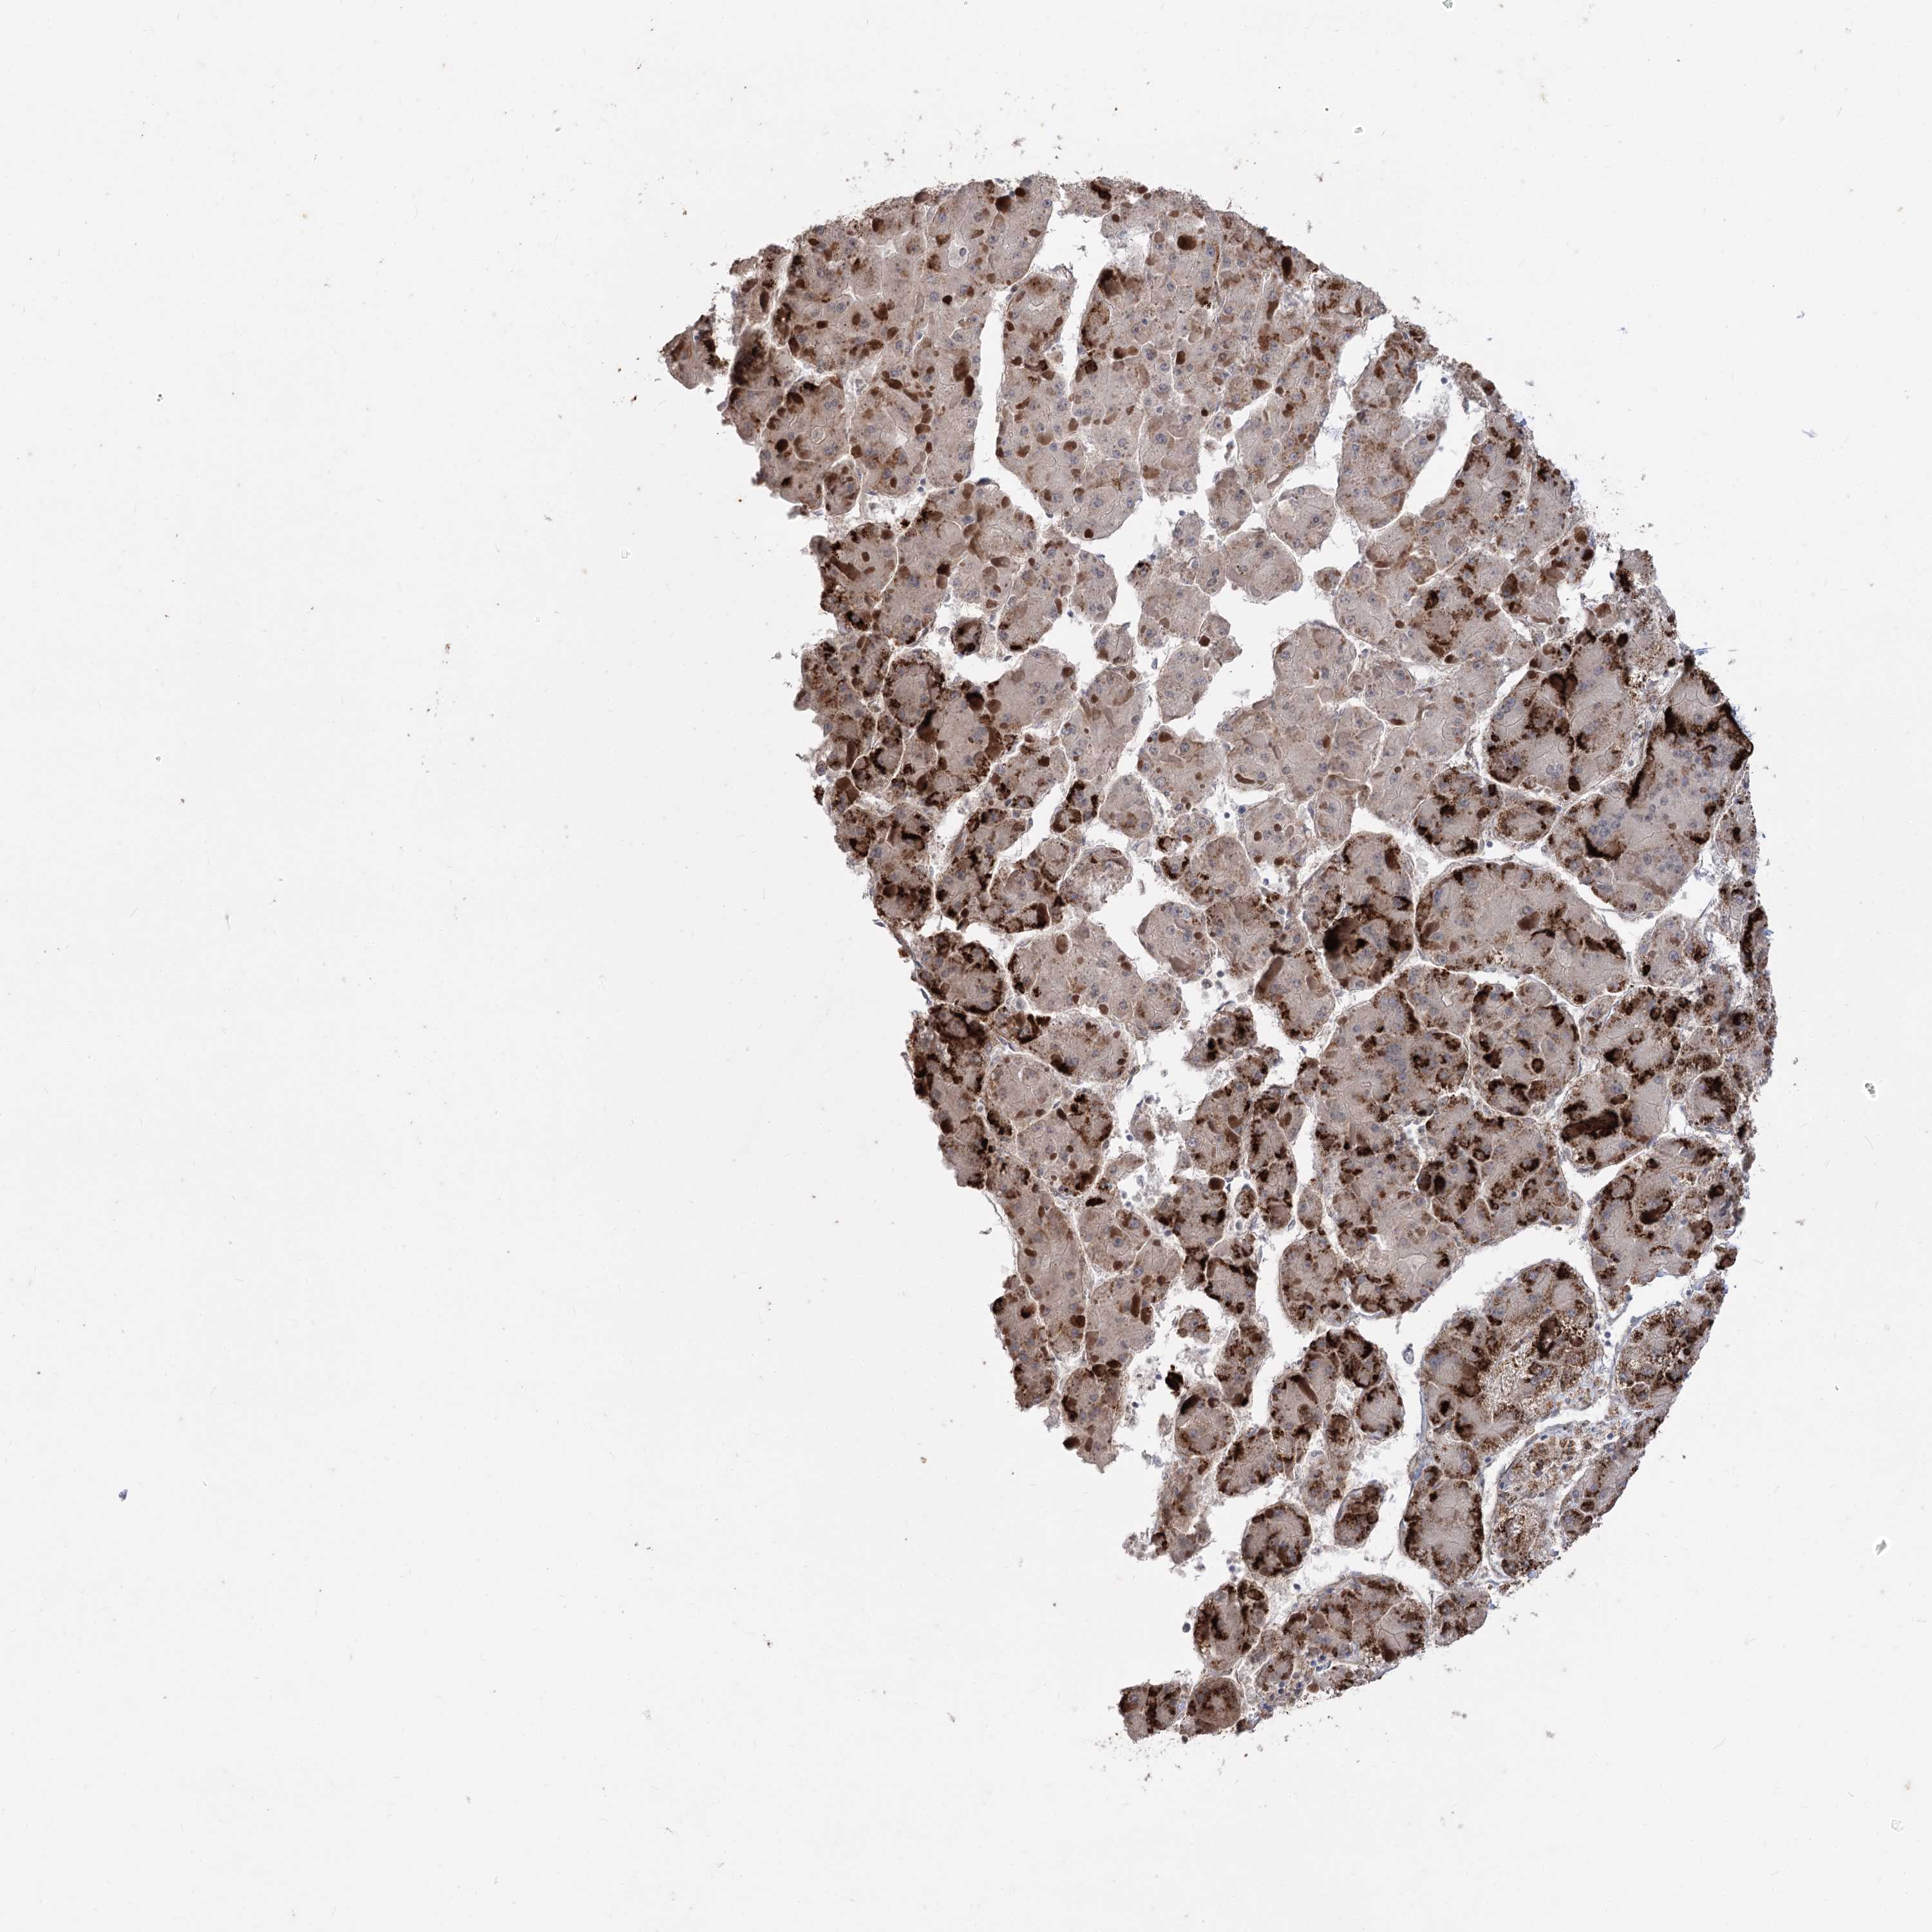

LIVER CANCER - Protein expressioni

A mouse-over function shows sample information and annotation data. Click on an image to view it in a full screen mode. Samples can be filtered based on level of antibody staining by selecting one or several of the following categories: high, medium, low and not detected. The assay and annotation is described here.

Note that samples used for immunohistochemistry by the Human Protein Atlas do not correspond to samples in the TCGA dataset.

Antibody stainingi

Antibody staining in the annotated cell types in the current human tissue is reported as not detected, low, medium, or high, based on conventional immunohistochemistry profiling in selected tissues. This score is based on the combination of the staining intensity and fraction of stained cells.

Each image is clickable and will lead to virtual microscopy that enables deeper exploration of all samples and also displays staining intensity scores, fraction scores and subcellular localization as well as patient and tissue information for each sample.

Antibody HPA035959

Antibody HPA035960

Staining

High

Medium

Low

Not detected

Intensity

Strong

Moderate

Weak

Negative

Quantity

>75%

75%-25%

<25%

None

Location

Nuclear

Cytoplasmic/membranous

Cytoplasmic/membranous,nuclear

Cholangiocarcinoma

Carcinoma, Hepatocellular, NOS